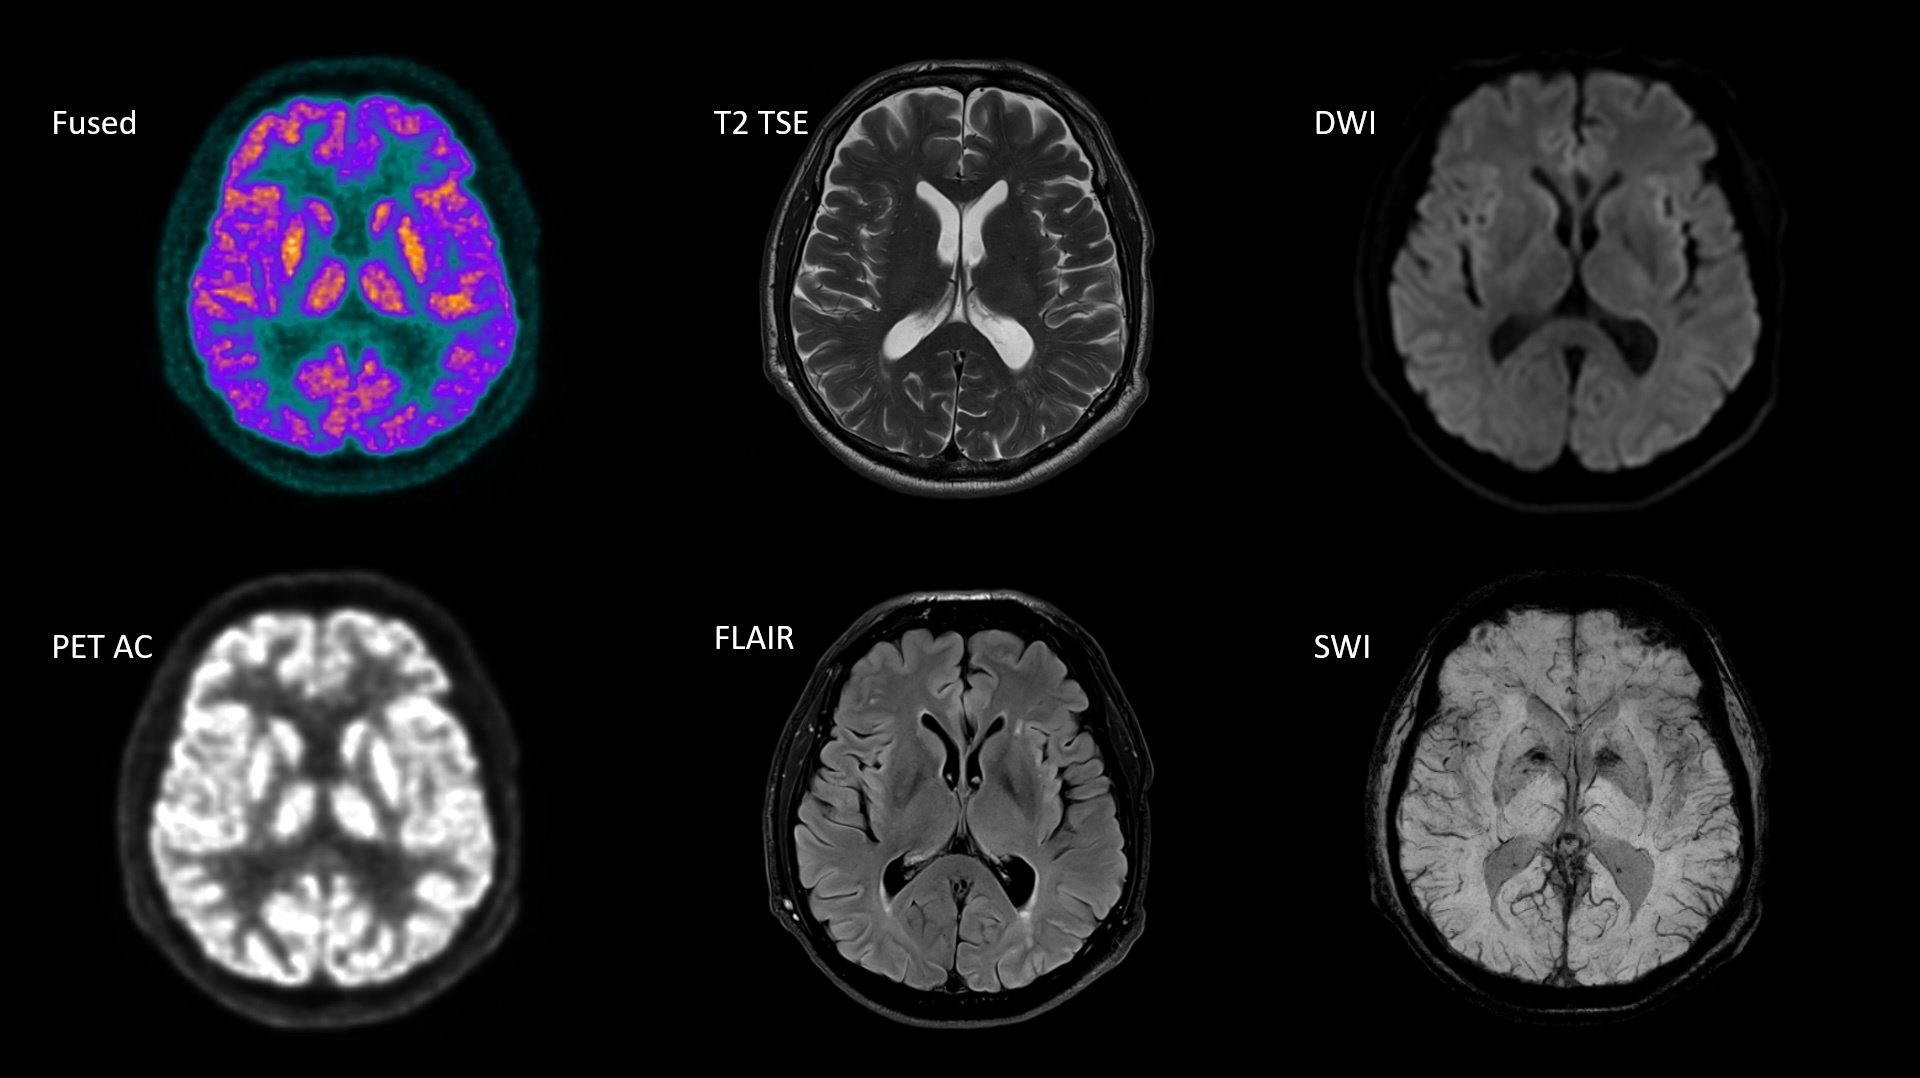

One stop shop multiparametric imaging for investigation of dementia

63-year-old male patient

Normal brain metabolism

• Injected dose: 184 MBq i.v.

• Uptake time: 76 min p.i.

• Sequences: T1 VIBE, T1 MPRAGE, FLAIR, DWI, SWI, T2 TSE

• MR TA: 12:20 min

• PET TA: 24:00 min6

Study-ID: 2aaaa3339 | Image courtesy of RIGS Hospital, Copenhagen, Denmark.